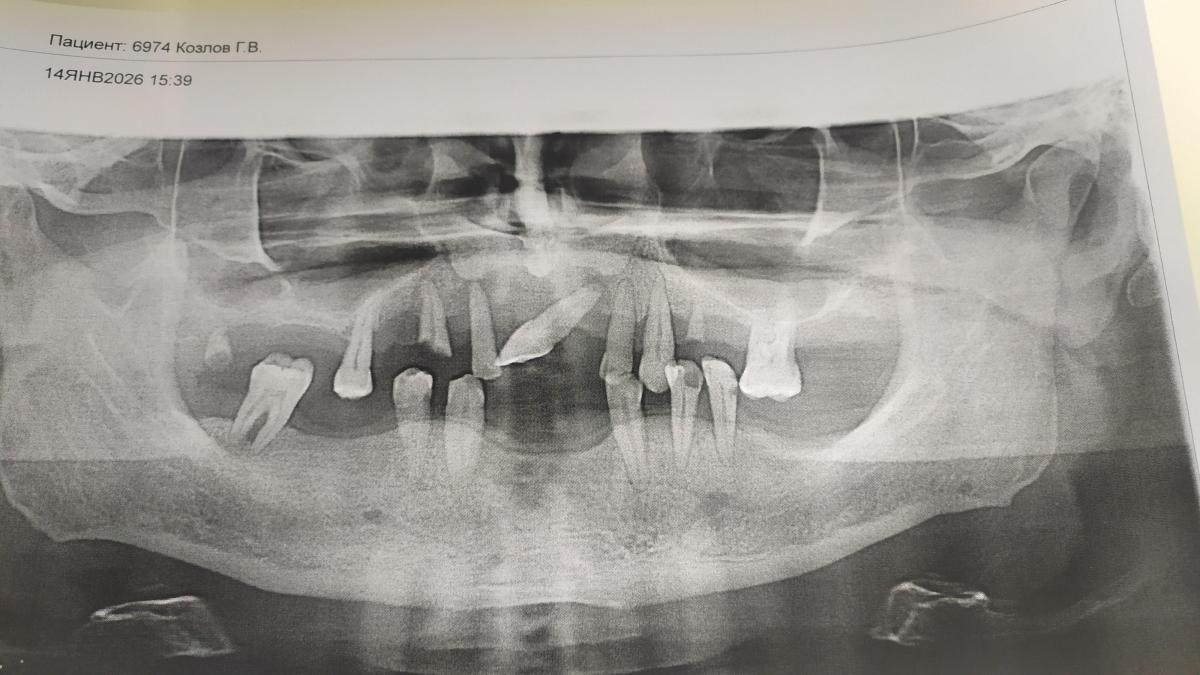

Всем здравствуйте. Я пациент. Подскажите пожалуйста, я запутался окончательно. Пародонтоз в последней стадии. Подвижность почти у всех зубов. Что скоро адентия- понимаю. Хотелось бы попытаться продлить расставание с остатками и использовать как опору съёмного протеза ( Акри фри советуют) . Окрашивание не пугает, Если ризорцин задержит остатки на месяцы - будет уже хорошо. Может ли сработать это и какие последствия я нк учитываю.? Огромное спасибо неравнодушным. Всё здоровья.

Есть такой, не бесспорный, метод, а может точнее - был!? Ну, может нижним зубам (кроме моляра), как-то продлит существование и то не надолго... Остальные - без вариантов!